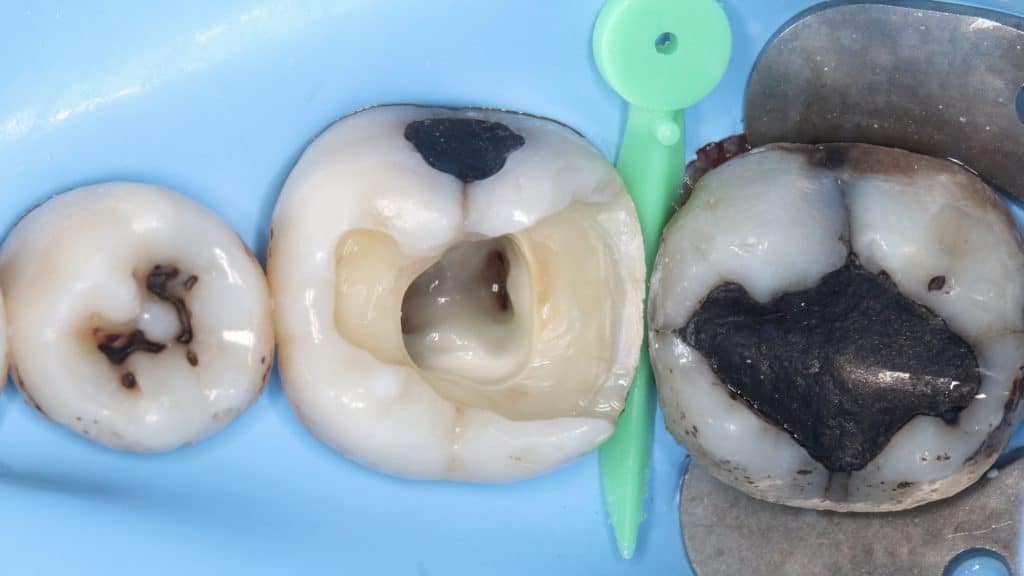

Tooth was cleaned form carious lesion, pulp tissue removed and irrigation protocol intimated (Normal Saline and Sodium Hypochlorite) to stop the bleeding. We decided to go with a minimally invasive approach. Distobuccal and distolingual cusps were weak.

Using LM Cusp Misura to check cusp hight and width starting with the distobuccal one. As it was thinner than 2 mm, the risk of fracture was high, so we decided to proceed to cusp coverage after endodontic treatment.

The same instrument was used to measure distolingual cusp, which was also too thin, so coverage was needed for this cusp as well.

Distal cusps were reduced, all unsupported enamel was removed.

Endodontic treatment was performed, and the gutta percha was cut at the canal orifice. The tooth was ready for overlay preparation.